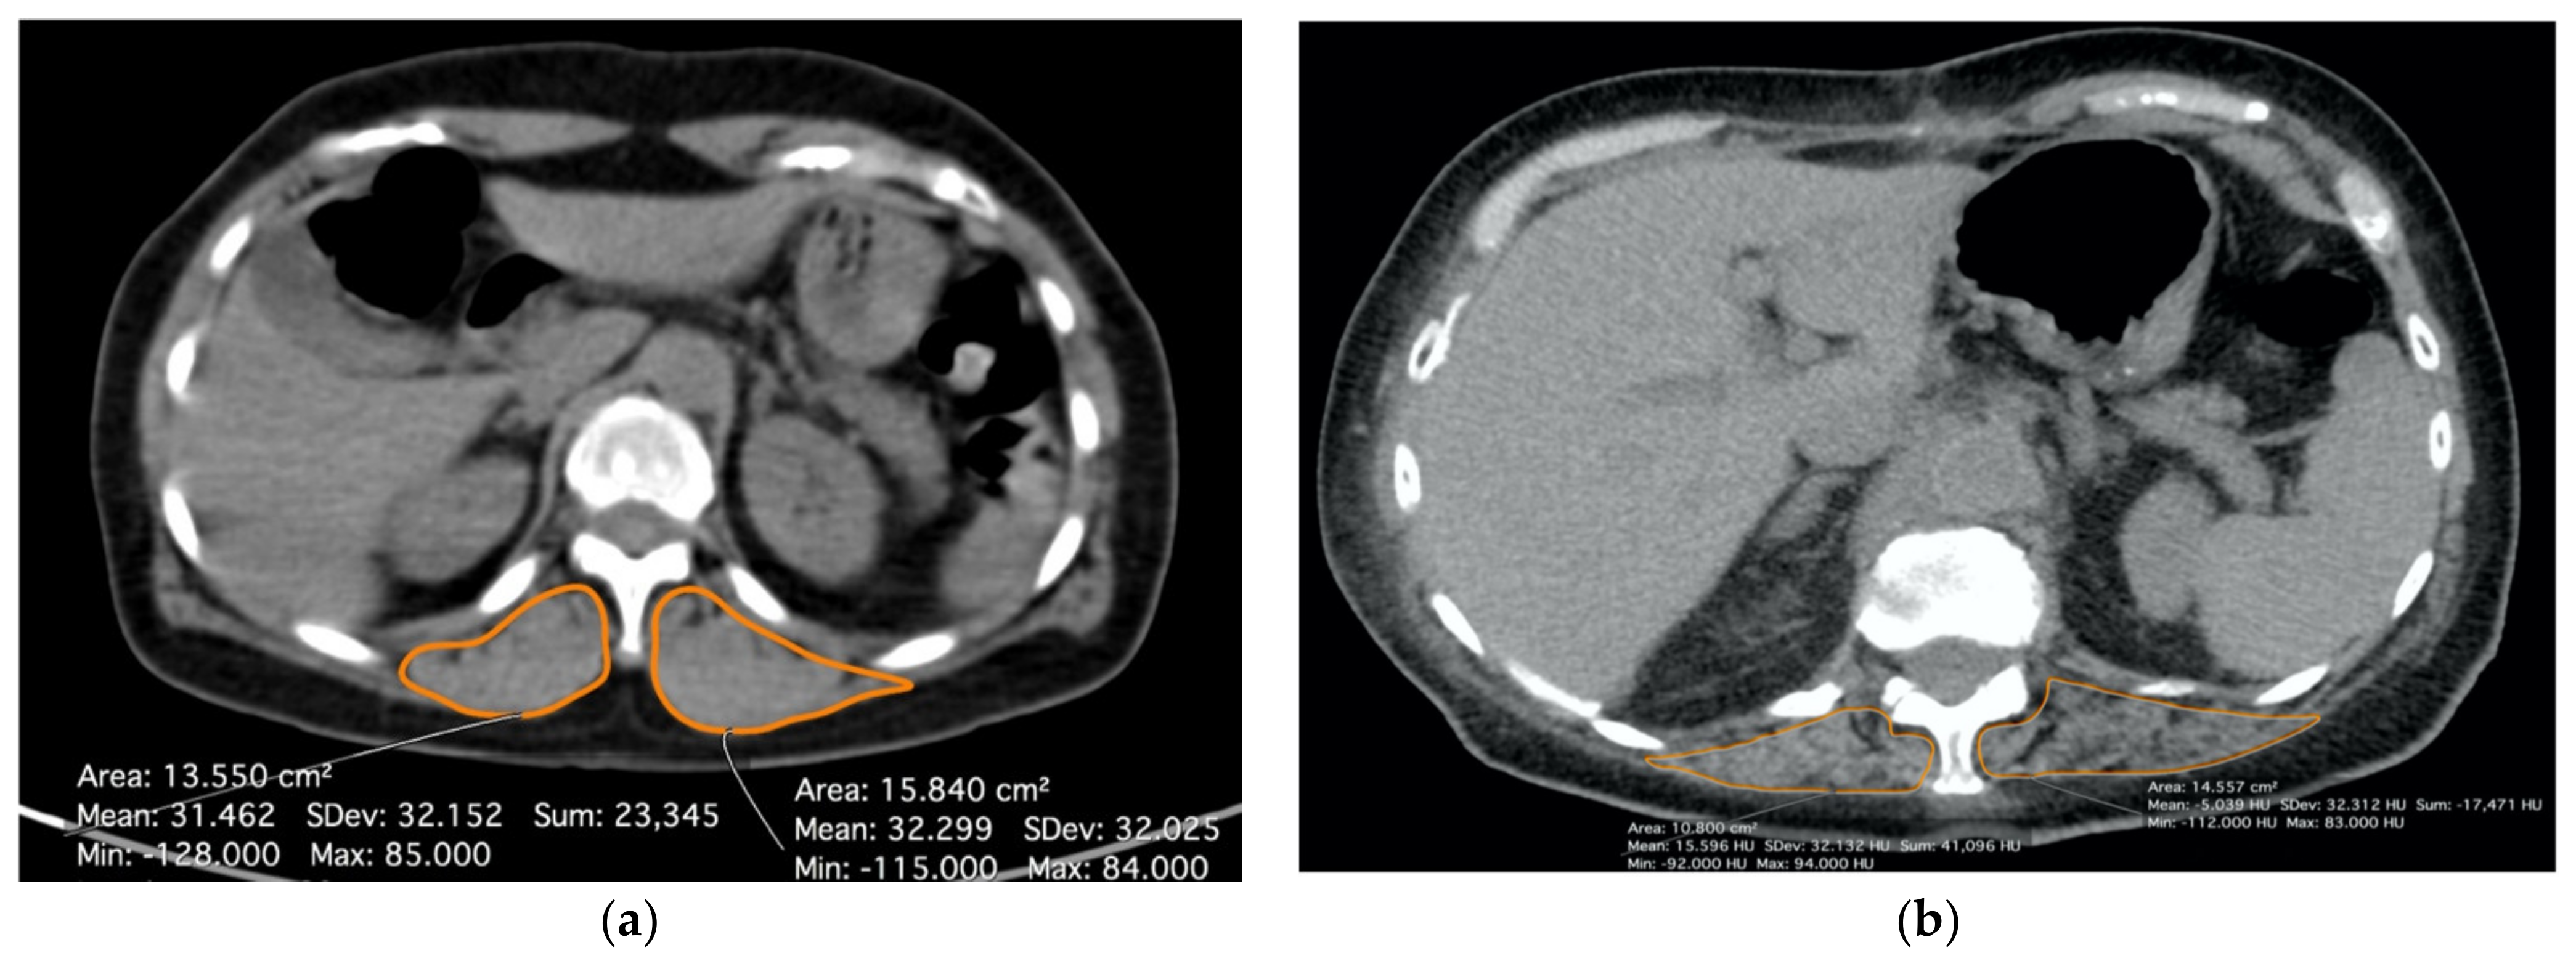

Pre- and post-operative CT scans without contrast and with a slice thickness of 3 mm were analyzed by two dedicated pulmonary radiologists with more than ten years of experience in musculoskeletal imaging. For each patient, the mean Hounsfield Unit (HU) value of the bilateral paravertebral muscles at the level of the 12th thoracic vertebra, using a free-hand region of interest, was calculated. All of the measures were performed with open-source software (Horos v3, www.horosproject.org (accessed between 1 January 2021 and 31 March 2021). According to the literature, a value of 30 HU was assessed as a cut-off to define a patient as sarcopenic [14,15,16,17]. Figure 2 shows how the radiological evaluation in a non-sarcopenic (a) and in a sarcopenic patient, respectively, (b) was performed.

Figure 2.

Radiological evaluation of sarcopenia at CT scan by measuring density of paravertebral muscles bilaterally (T12 level). (a) Patient without sarcopenia (muscular density > 30 HU); (b) Patient with sarcopenia (muscular density < 30 HU).